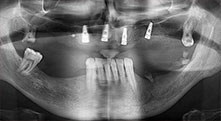

Pr Bratu : Nous avons volontiers recours à la technique sandwich pour les augmentations mandibulaires latérales. La préparation d'un couvercle osseux est réalisée à l'aide de la scie piézoélectrique et le fragment crestal est fixé à l'aide de microvis. Nous plaçons un mélange de matériau de substitution osseuse autologue et xénogénique entre les deux. Cela fonctionne très bien. Il faut toujours s'assurer que les coupes verticales aient des dimensions suffisantes lors du clivage de la crête alvéolaire dans la mandibule. Sinon, l'os risque de se casser facilement.